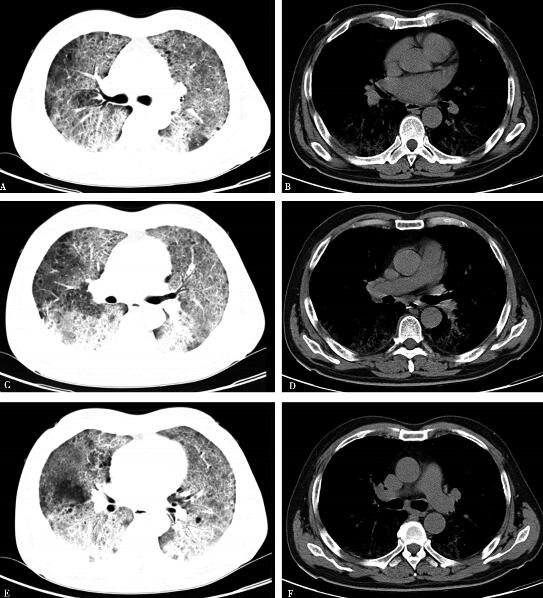

6.2010年4月20日胸部CT(图1):双肺野透光度降低,双肺弥漫分布磨玻璃影,可见支气管气象,胸膜下及双肺下叶小叶间隔增厚。

图1

胸部影像学示双肺野透光度降低,双肺弥漫分布磨玻璃影,可见支气管气象,胸膜下及双肺下叶小叶间隔增厚为主;动脉血氧分压降低,肺泡动脉氧分压差增大。同时双肺可闻及帛裂音,进一步支持初步诊断“间质性肺疾病”。结合患者长期大量吸烟史,分型首先考虑为脱屑型间质性肺炎可能性大,建议行纤维支气管镜检查协助确诊,但患者及家属拒绝。末梢血白细胞计数、中性粒细胞百分比均增高,考虑存在合并细菌感染可能,感染部位首先考虑为肺部,病原学尚不清楚。血红蛋白升高与长期缺氧导致代偿性增高有关;尽管非肿瘤性间质性肺疾病由于成纤维细胞增生可导致血CEA轻度升高,但本例患者血CEA高达34.59ng/ml,故不能除外肿瘤(尤其腺癌)的可能,需要进一步完善检查并密切随诊。虽然血CEA等均增高,但影像学无肺部肿瘤依据,考虑与肺部基础病变相关,进一步除外其他部位肿瘤并密切随诊。结缔组织疾病、心脏疾病可除外。